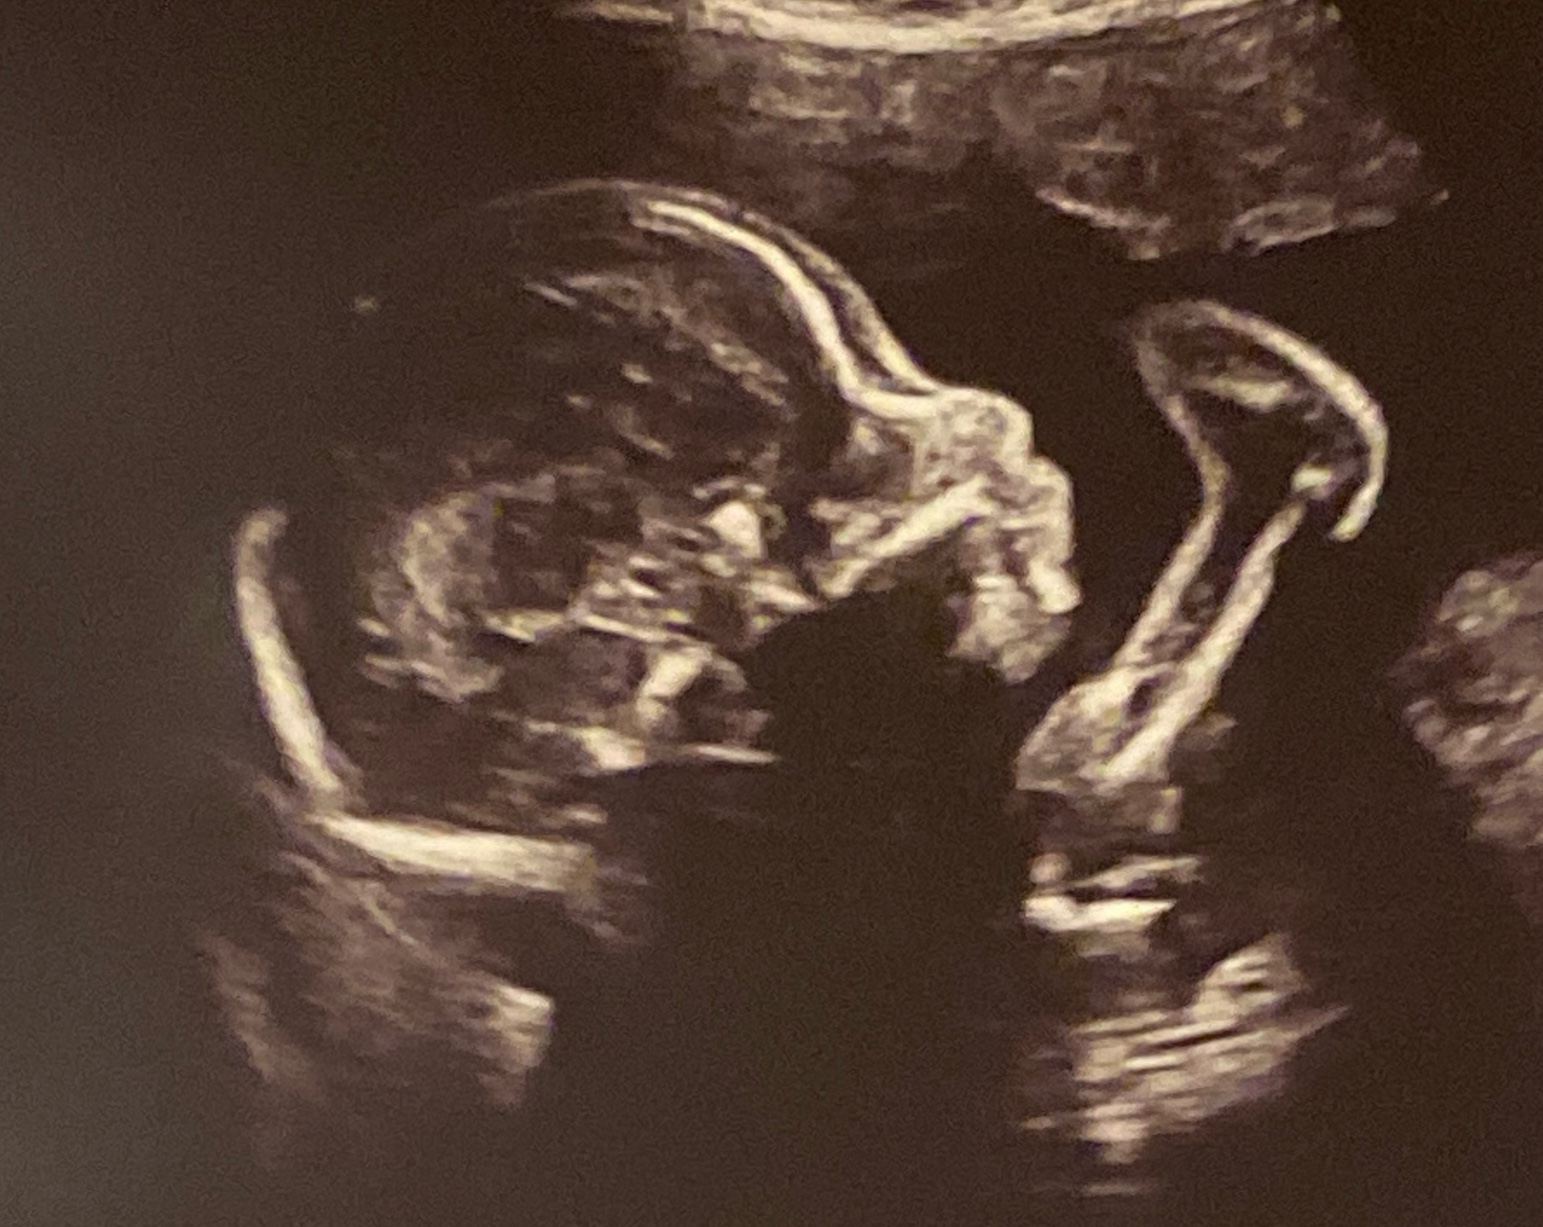

또 하나 고민이 됐던 건 아기 크기였습니다. 출산 예정일이 다가올수록 아기 체중이 빠르게 늘었고, 이미 3kg에 가까운 상태였습니다.

게다가 남편이 머리가 큰 편이라… 초기 초음파부터 몸무게랑 다리길이는 다 중간에 있었는데 머리둘레만큼은 상위 25%에 항상 들어갔었거든요.. “이거 자연분만 쉽지 않을 수도 있겠는데?”라는 생각이 들었습니다. 의사 선생님도 비슷한 의견이기도 했구요.